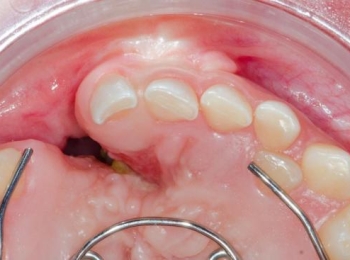

تعتبر زراعة عظم في اللثة أحد الإجراءات التجميلية الدقيقة التي تجعلك تستمتع بقاعدة قوية قبل تركيب الأسنان الصناعية، ...